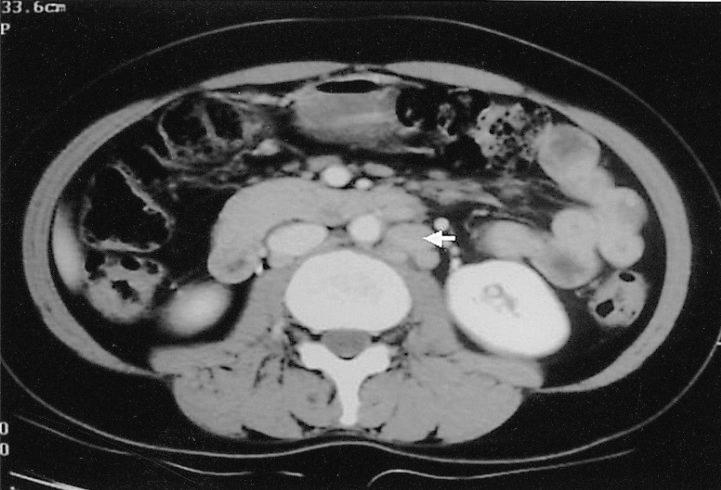

伴有嗜酸性粒细胞增多综合征及胸腔积液的外周T细胞淋巴瘤,非特指型(PTCL-U)

Hypereosinophilic syndrome (HES) is a clinical disorder characterized by persistent eosinophilia and systemic involvement, in which a specific causative factor for the eosinophilia cannot be verified during a certain period of time. There have been only a few reported cases of this syndrome associated with malignant lymphoma. We report a case of peripheral T-cell lymphoma-unspecified with hypereosinophilic syndrome. The patient was a 42-year-old woman with an uncontrolled fever and a sore throat. Eosinophilia was observed on the peripheral blood smear. We confirmed the diagnosis by bone marrow and liver biopsies:. A bone marrow aspiration demonstrated markedly increased eosinophils (24.8%), and a liver biopsy demonstrated infiltration by scattered eosinophils and atypical lymphoid cells, which were confirmed to be T-cell lymphoma cells. This case was a distinctive presentation of peripheral T-cell lymphoma with hypereosinophilic syndrome, probably due to a paraneoplastic condition.

高嗜酸性粒细胞综合征(HES)是一种以持续性嗜酸性粒细胞增多和全身受累为特征的临床疾病,在一定时期内无法证实嗜酸性粒细胞增多的特定致病因素。与恶性淋巴瘤相关的该综合征报告病例仅有少数。我们报告一例伴有高嗜酸性粒细胞综合征的外周T细胞淋巴瘤(非特指型)。患者为一名42岁女性,有持续发热和咽痛症状。外周血涂片可见嗜酸性粒细胞增多。我们通过骨髓和肝脏活检确诊:骨髓穿刺显示嗜酸性粒细胞显著增多(24.8%),肝脏活检显示有散在嗜酸性粒细胞和非典型淋巴细胞浸润,经证实为T细胞淋巴瘤细胞。该病例是外周T细胞淋巴瘤伴高嗜酸性粒细胞综合征的一种独特表现,可能是由于副肿瘤状态所致。